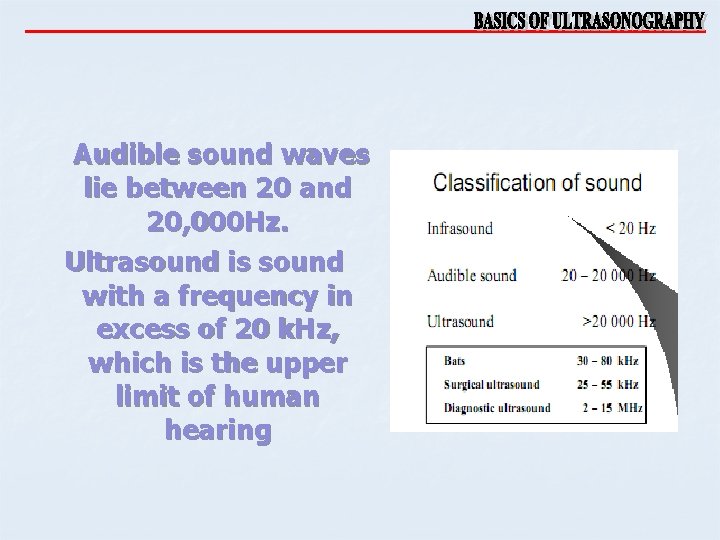

Audible sound waves lie between 20 and 20, 000 Hz. Ultrasound is sound with a frequency in excess of 20 k. Hz, which is the upper limit of human hearing